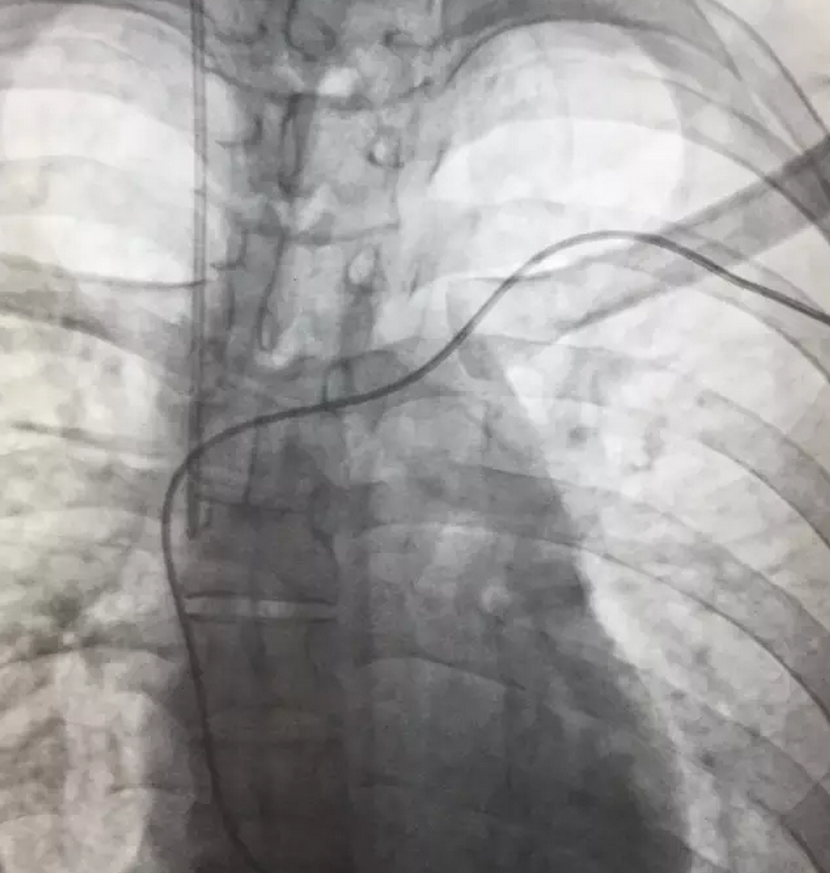

入院后,心內(nèi)科的值班醫(yī)生考慮,患者在院前曾出現(xiàn)抽搐、心跳停搏現(xiàn)象,心肌炎較為嚴(yán)重,心臟隨時(shí)有再次發(fā)生停搏的可能,于是馬上通知上級(jí)醫(yī)生進(jìn)行緊急會(huì)診,專家會(huì)診后決定,立即為病人緊急手術(shù)安裝心臟保護(hù)裝置-臨時(shí)起搏器。

手術(shù)過(guò)程有驚無(wú)險(xiǎn),手術(shù)在介入科DSA引導(dǎo)下進(jìn)行,在臨時(shí)起搏導(dǎo)管送入到右心室時(shí),病人突然出現(xiàn)神志不清、四肢抽搐,心電監(jiān)護(hù)顯示患者再次出現(xiàn)心室停搏,手術(shù)醫(yī)生們臨危不亂,果斷為病人實(shí)施各項(xiàng)搶救措施的同時(shí)立即連接并啟動(dòng)起搏器。病人心跳馬上恢復(fù),隨后轉(zhuǎn)醒。經(jīng)過(guò)差不多一個(gè)小時(shí),患者順利安裝了臨時(shí)心臟起搏器,并轉(zhuǎn)入心內(nèi)科重癥監(jiān)護(hù)病區(qū)密切觀察和治療。